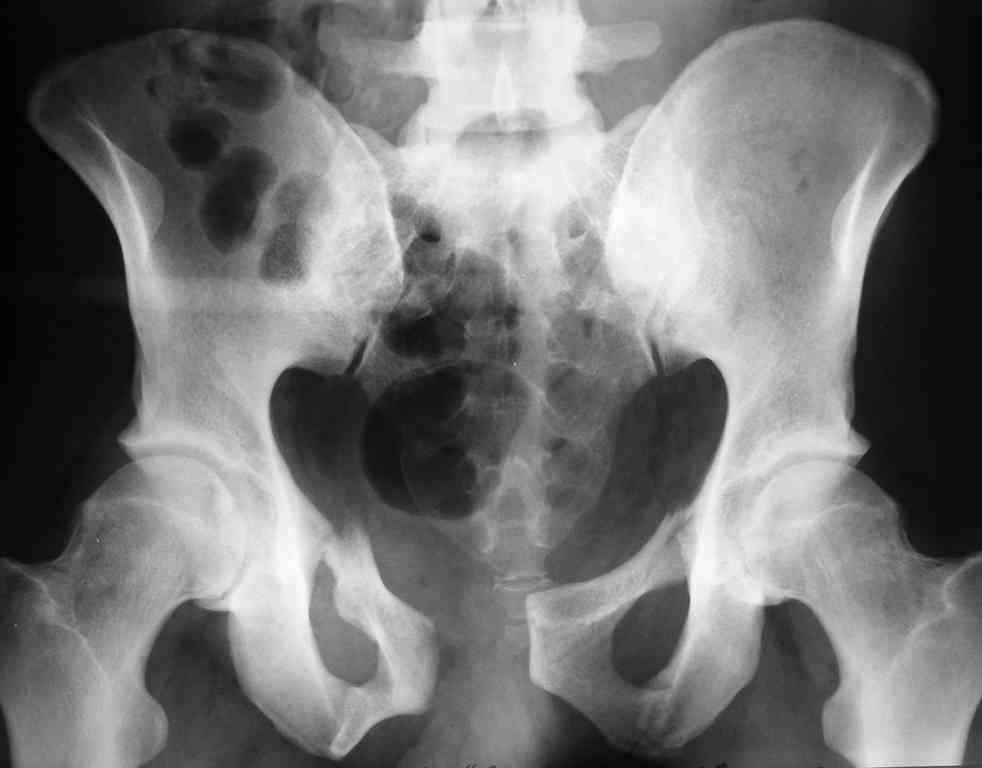

Уважаемые коллеги! опять вопрос по повреждению таза. Больной получил производственную травму 10 дней назад - удар балкой около 3 тонн в область верхней трети правого бедра и лона.

Был диагностирован перелом "типа бабочки" и повреждение уретры. Сделана цистостома. У насв отделении 3 дня. Имеется огромная флюктуирующая гематома с "галифе"-образной деформацией обеих бедер. Пнкционно эвакуировали в несколько приемов из подфасциальных полостей на бедрах около 3 литров геморрагического отделяемого с последующей эластической компрессией. При пункциях выявлено сообщение полостей на бедрах - видимо через поравннуюдиафрагму дна и полость таза - при удалении крови справа уменьшался объем левого бедра. Какой то активности проявялять покабоимся - аппаратная фиксация через отслоенные ткани представляется чреватой нагноением, открытая фиксация в условиях такой гематомы тоже не радует. Хотелось бы услышать ваше мнение

Типичная картина Morel-Lavallee повреждения.

Безуспешны многочисленные шприцевые эвакуации, мы лечим в операционной, доступом на латеральной поверхности, открытием образования с удалением и очисткой полости щеткой. Закрываем с дренажной трубкой (в архивах сайта) и накладывается мягкая повязка Спика из нескольких слоев эластичной повязки.

Следующим этапом через 5-6 дней приступаем к фиксацию повреждения таза, иначе прооперериванные на фоне Morel-Lavallee повреждения осложняются инфицированием послеоперационной раны.